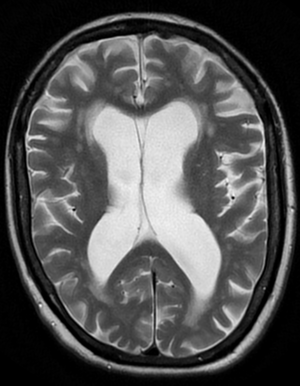

Magnetic resonance imaging (T2-FLAIR) showing vascular dementia